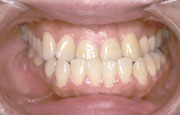

矯正の症例

| 【Before】 | 【After】 | |